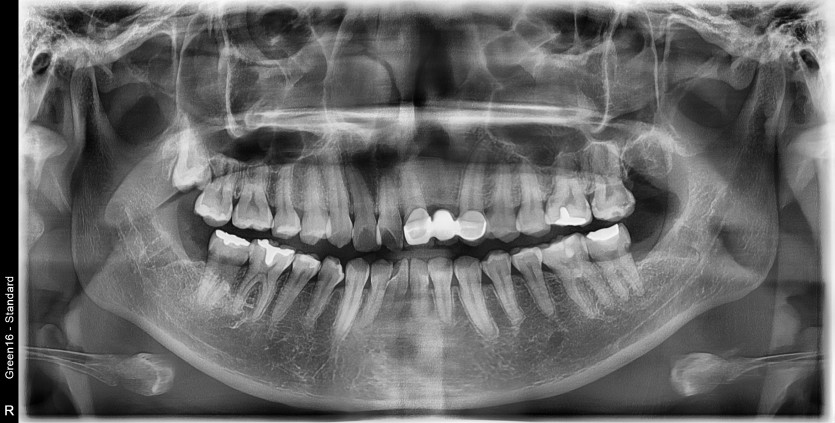

#28,38,48 사랑니 발치

구강 외과 전문의가 당일 발치했습니다.